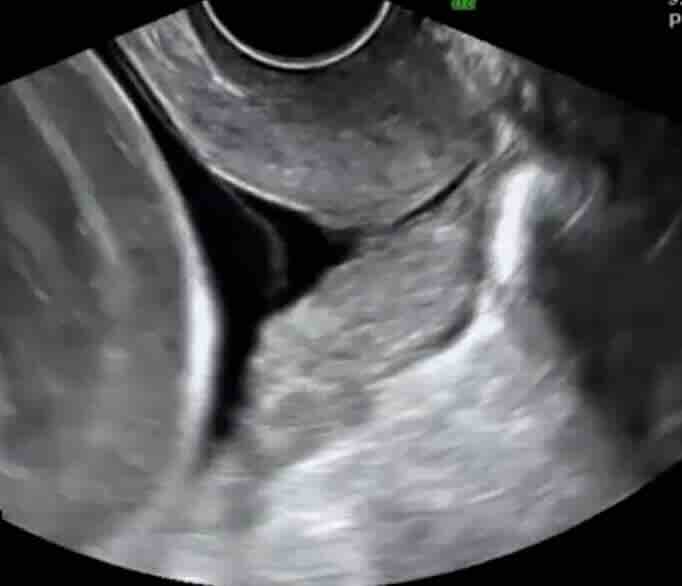

Rahim filmi, rahim iç boşluğunu ve tüplerin açıklığını değerlendirmek için yapılan özel bir röntgen görüntüleme yöntemidir.

Bu işlem sırasında rahim içine kontrast madde verilir ve röntgen altında görüntü alınır. Eğer tüpler açıksa kontrast tüplerden karın içine yayılır. Eğer tıkanıklık varsa kontrast ilerlemez ve bu durum net şekilde görülür.

Kontrast madde kontrollü verilir

Röntgen görüntüsü alınır